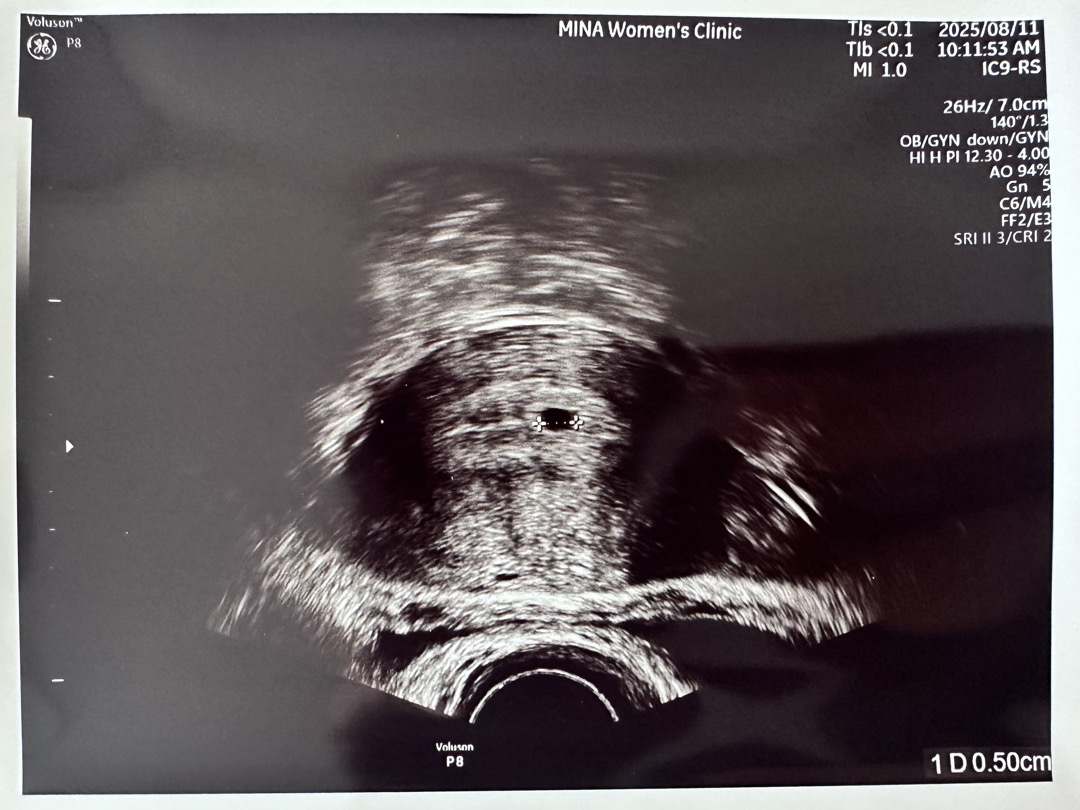

4주차 첫 초음파 아기집🍼✨

안녕하세요! 아이 기다린지 14개월.. 다 포기하고 쉬고 있었는데 정말 기적적으로 아이가 찾아왔어요! 마지막 생리 시작일 7월5일이구요 지난 8일 금요일 피검사 hcg 969 였어요 오늘 남편이랑 같이 병원가서 초음파 보고 왔습니다💙 딱 초음파 하자마자 보이는 아기집!! 5주2일 예상했는데, 예상보다 늦게 생겨서 4주4일로 예상 출산 예정일은 4월16일 같다고하시네요! 2주 뒤에 오라고 하시는데 너무 길어서 어떻게 기다려하나 막막스.. 다들 저와 같으시죠..? 🥹🥹